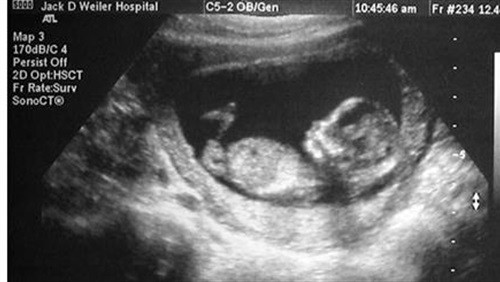

طرق ووسائل وتوجيهات طبية لمعرفة جنس الجنين لا بد من اللجوء إلى المعرفة الطبية للتوصل إلى نتيجة حقيقية في هذا الشأن وهنا نورد أبرز النقاط والطرق ووسائل التي يتبعها الطب للحكم على جنس المولود، وبعض الطرق ووسائل الشعبية لذلك: التصوير الصدوي إن الكشف عن جنس الجنين بالتصوير الصدوي في الثلث الأول من الحمل هو أمرٌ ثانويٌ، أي إنّه يمكن القيام به دون أن يكون عماد هذا الاستقصاء الطبي. تحديد جنس الجنين في الثلث الأول من الحمل يتم بالفحص الدقيق للبرعم التناسلي بالتصوير الصدوي، ومن ناحية التطوّر الجنيني هذا البرعم التناسلي يبدأ بالتشكل والتميّز نحو الأسبوع التاسع من اِنقطاع الطمث. في وقتنا الحاضر يجب عدم تحديد جنس الجنين بدراسة البرعم التناسلي قبل الأسبوع الثاني عشر من انقطاع الطمث، ذلك لأن قيمة الخطأ تصل إلى الأربعين بالمئة، هذا يعني أنّ إمكانية النجاح في الفحص وتشخيص لا تتجاوز إلا بقليل فعل المصادفة أي مناصفة بين الذكر والأنثى. الحكم على البرعم التناسلي اعتباراً من الأسبوع الثاني عشر من الطمث : يمكن بشكلٍ مختصر الحكم على طبيعة جنس الجنين حسب شكل البرعم التناسلي وذلك وفقاً للخصائص التالية: عند الجنين الأنثى البرعم التناسلي يتجه الأسفل ليأخذ وضعاً أفقياً. عند الجنين الذكر البرعم التناسلي يتجّه نحو الأمام ليأخذ وضعاً شبه أُفقي. من المفضل أن يكون الفاحص متأنٍ في عمله خاصة عندما يكون عنده الوقت الكافي وذلك من أجل تحديد الزاوية المتشكلة ما بين مستقيمين، الأول مماس للسطح القطني العجزي للجنين والثاني مماس للوجه البطني للبرعم التناسلي، فقياس هذه الزاوية يجب أن يجرى على الجنين وهو في وضعٍ يسمح بالحصول على مقطعٍ طولي متوسّط دون أي اِنحراف وإلا فإنّ الخطأ في تحديد جنس الجنين يزداد. في الحالة التي يكون فيها المستقيمان السابقان متوازيين ولا يلتقيان فإنّ جنس الجنين على الأرجح أنثى، ونسبة الخطأ في تحديد جنس الجنين في هذه الحالة تقدر بـ (0.9% و 3%) وفي كل الدراسات نسبة الخطأ في الفحص وتشخيص هي أعلى عندما يبشر الفاحص أنّ الجنين هو أنثى. في الحالة التي يتقاطع فيها المستقيمان السابقان ليرسما زاوية قيمتها أعلى من ثلاثين درجة مئوية، جنس الجنين هو على الأرجح ذكر، واحتمال الخطأ في هذه الحالة يقدر بـ (0.2%)